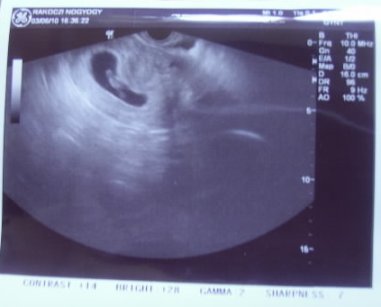

A tapolcai UH szerint ma 11,4mm-es a CRL, ami nekem furcsa.. Amikor kórházba kerültem, aznap mért a doki 5,4mm-t, aztán rá 3 napra a saját orvosom 10mm-t mért babánként, és ma, egy héttel később 11,4mm.. Most valamelyikük rosszul mért volna, vagy csak ilyen lassan növekszenek?